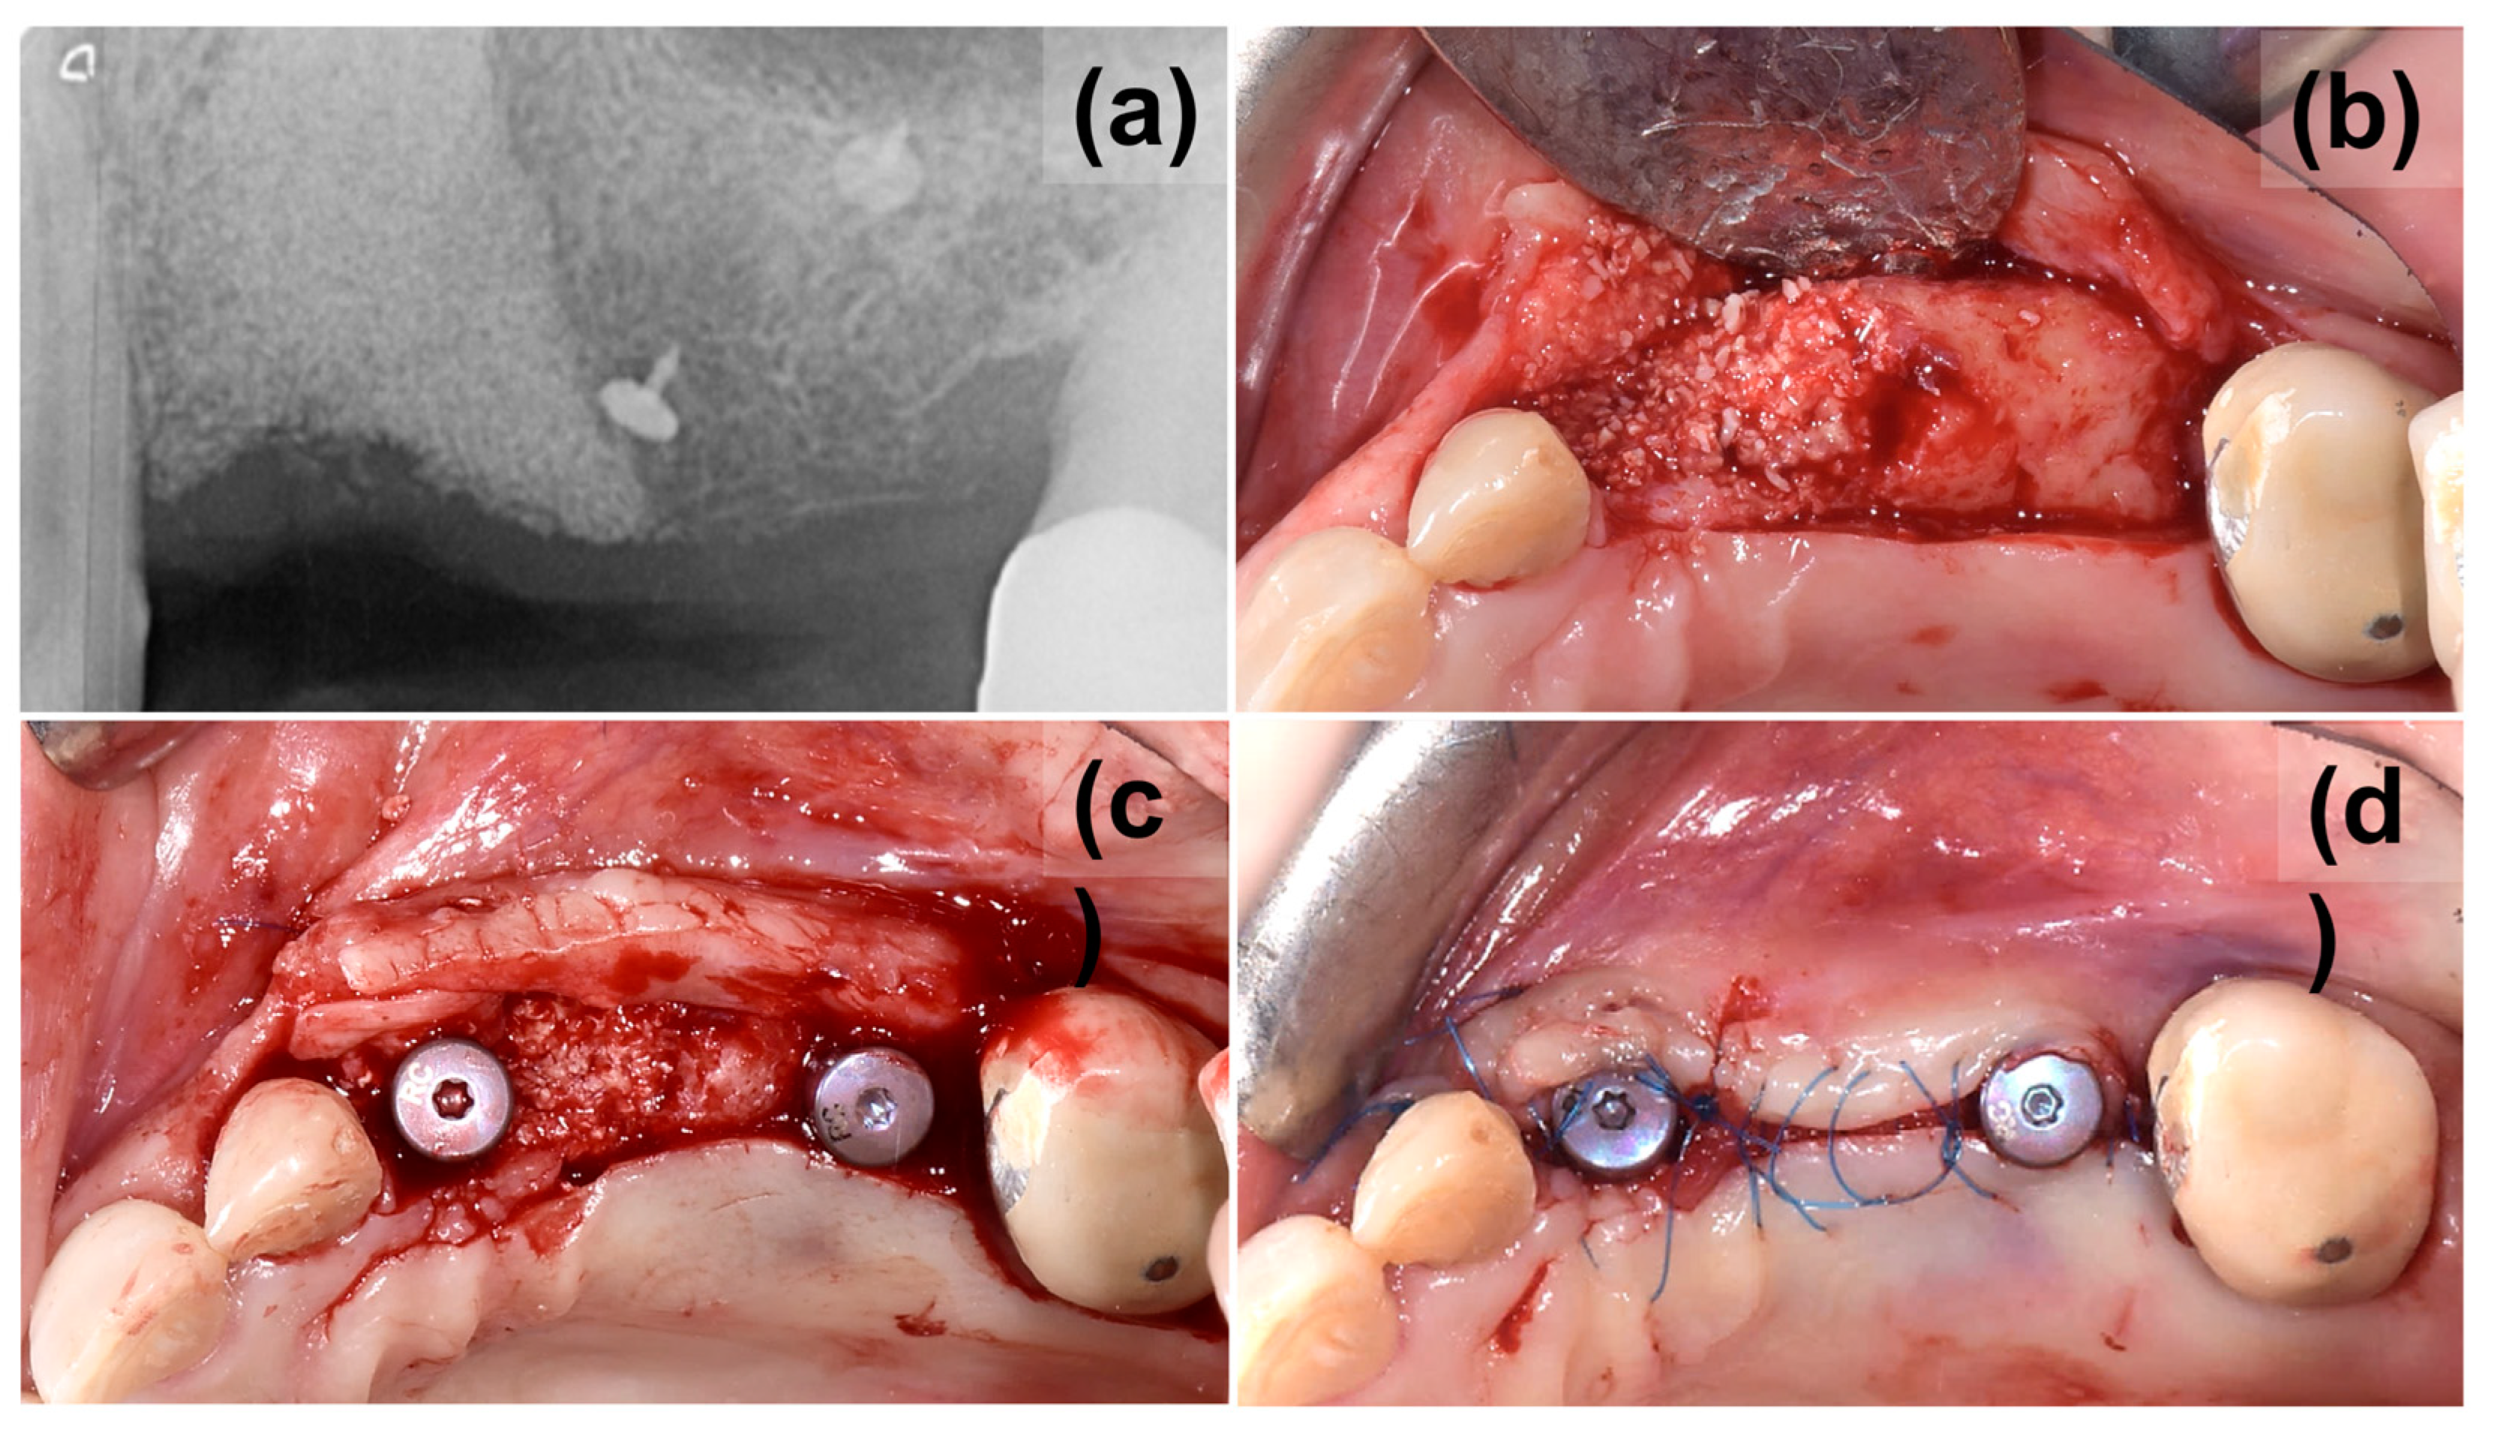

2. Case Presentation